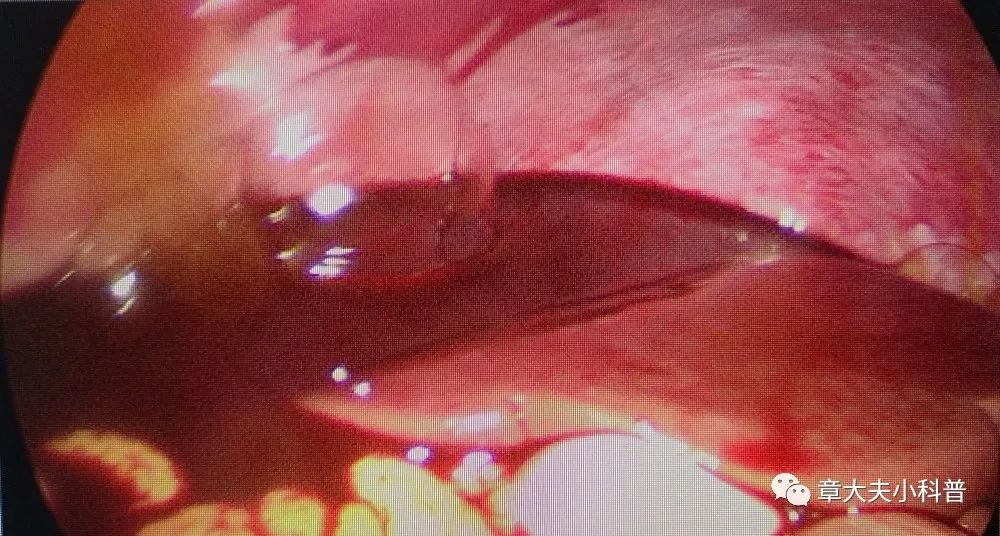

腹腔镜探查

见右侧卵巢

黄体破裂,

腹腔内出血,

1300ml